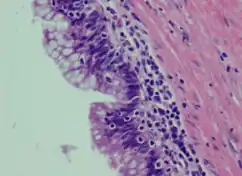

| Atypical goblet cells with focal tufting. | |

Mucinous cystadenocarcinoma is a type of tumor in the cystadenocarcinoma grouping.

It can occur in the breast[1] as well as in the ovary.[2] Tumors are normally multilocular with various smooth, thin walled cysts. Within the cysts is found a haemorrhagic or cellular debris.[2]